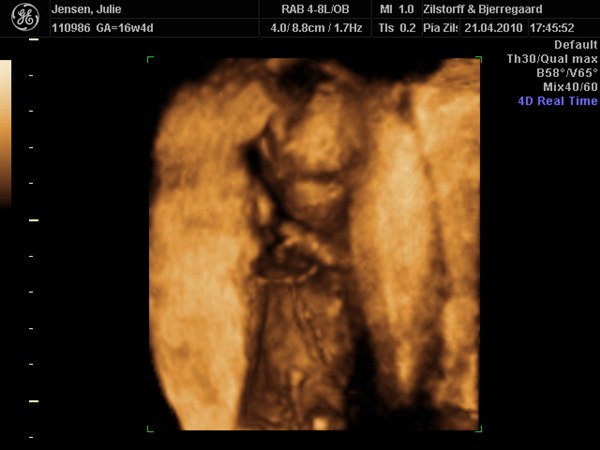

Det var en lille pige der tittede frem på skærmen igår

Desværre var hun en lille puttegøj så der blev ikke rigtig nogle "gode" billeder.... Da hun putter sig godt med moderkagen og den der væg der så hun ligger lige i sådan et hul :) Men har fået tid til i uge 28 igen :) Så ville hun ikke lade mig gå uden et par perfekte billeder :) Smiler....

Her er lidt billeder :)